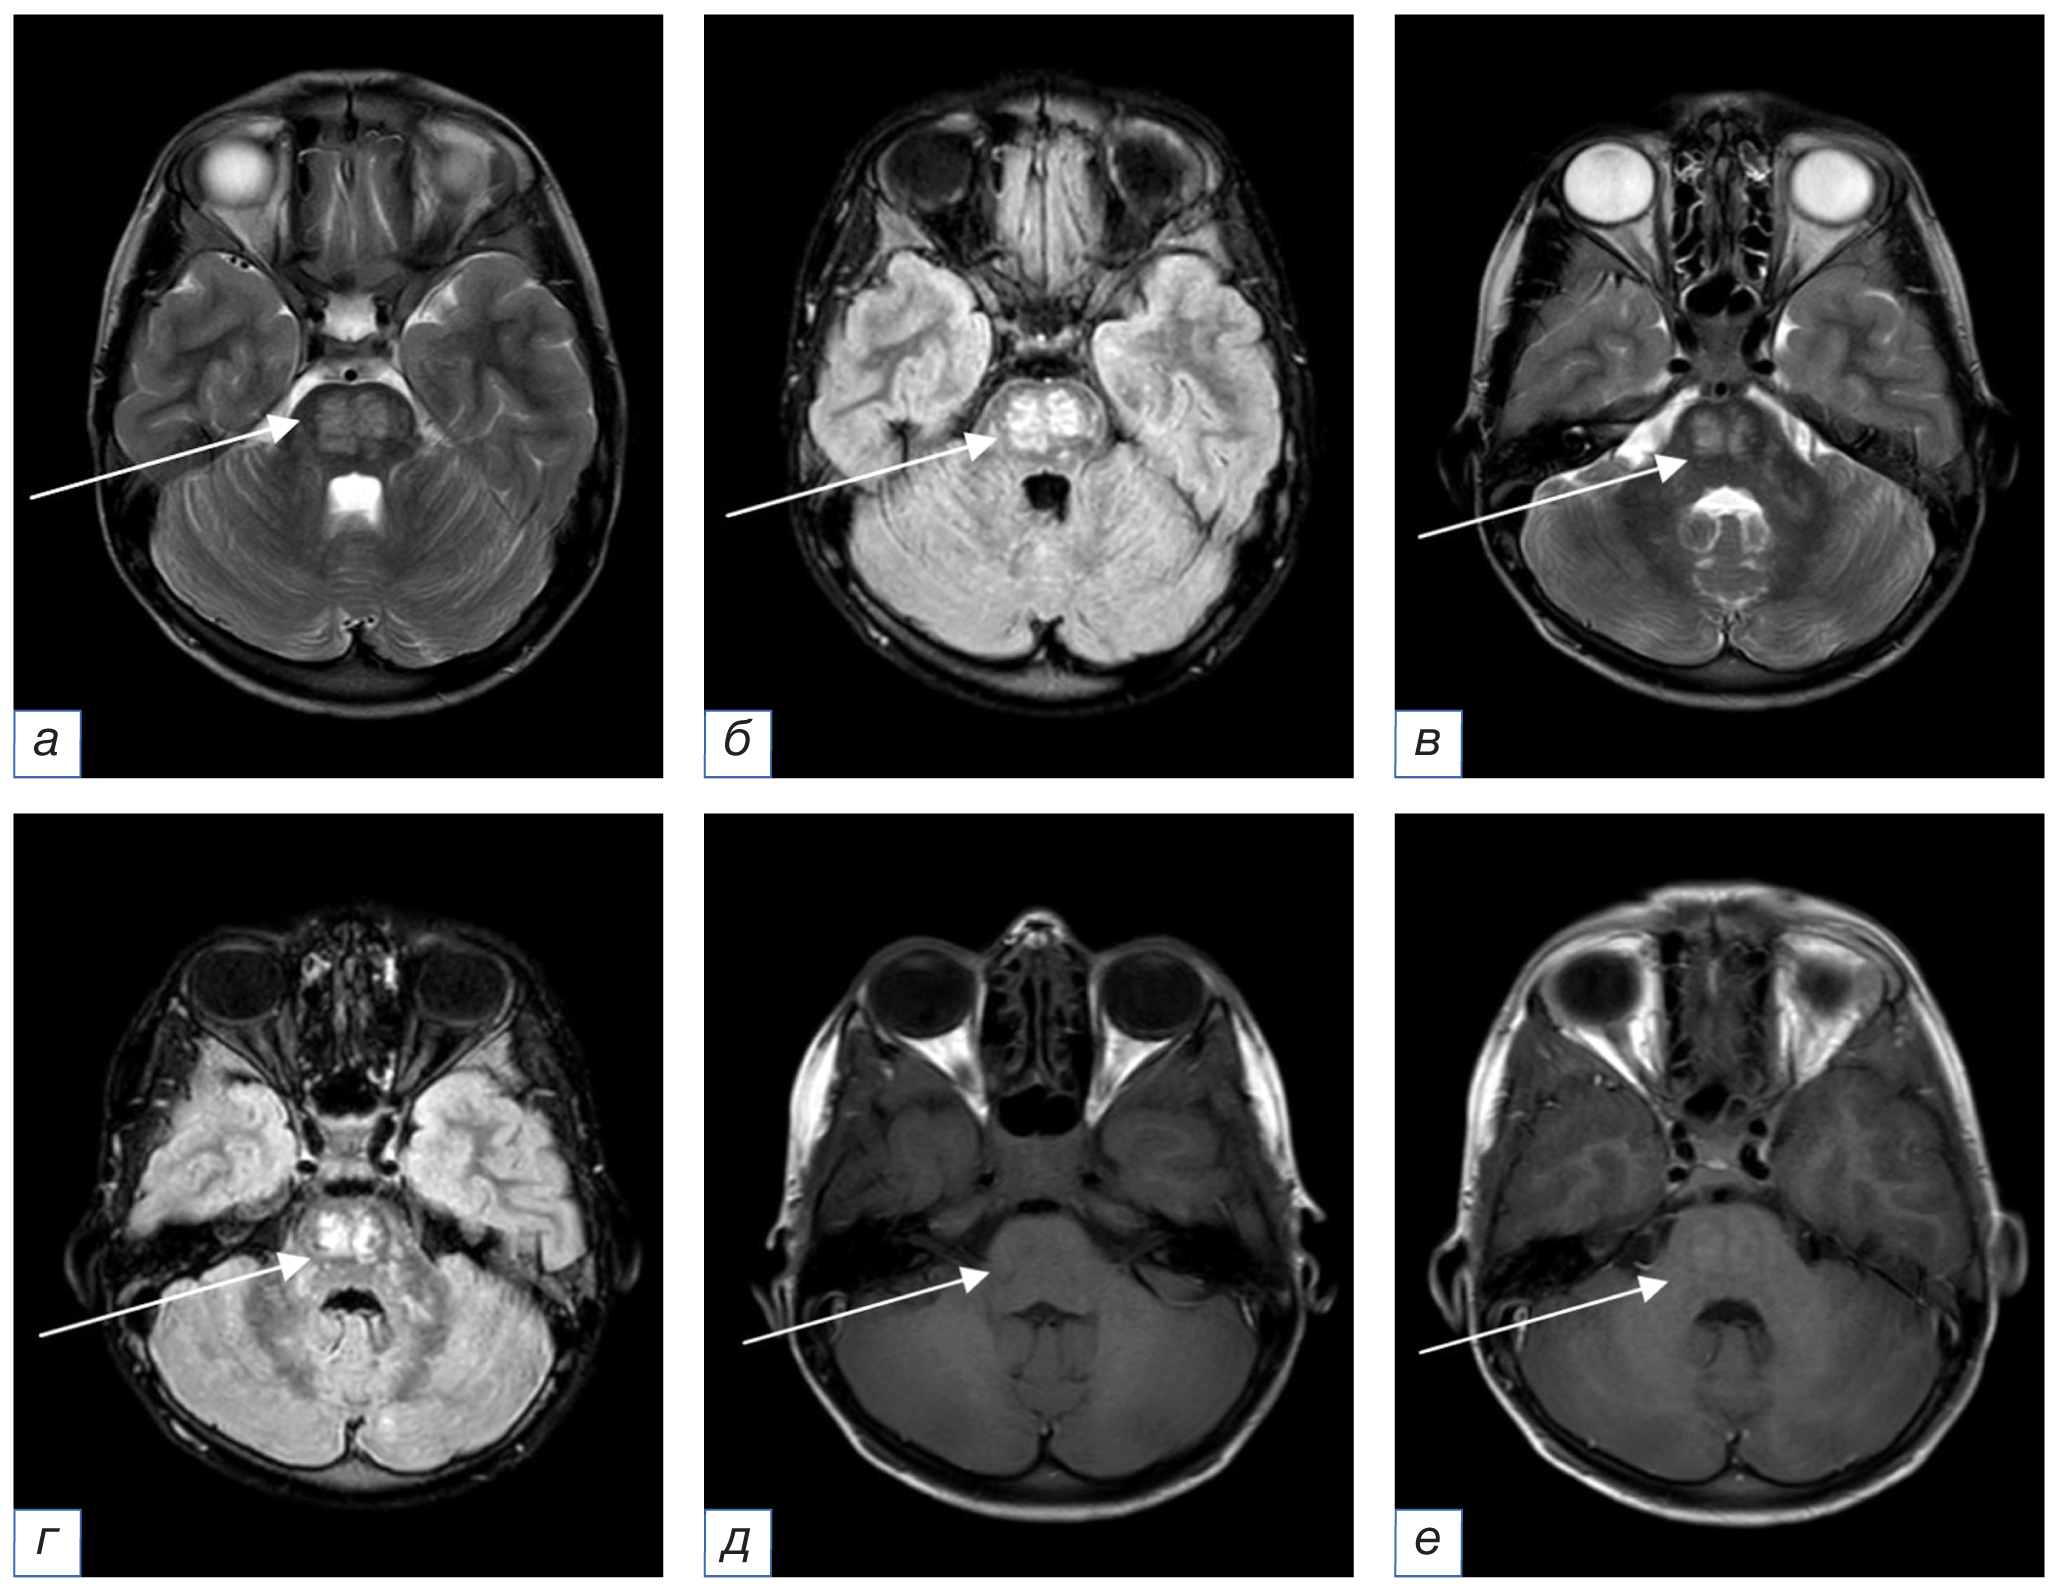

16.08.2021. При проведении повторной МРТ с внутривенным контрастным усилением (рис. 2) сохранялись ранее выявленные очаги прежних размеров и структуры. На фоне контрастирования долженствующего накопления контрастного вещества очагами не определялось, вероятно, за счет ранее проведенного курса пульс-терапии.

Рис. 2. Повторное, после 5 дней пульс-терапии, МРТ головного мозга в аксиальной плоскости с внутривенным контрастным усилением от 16.08.2021 (a, в — режим Т2-ВИ; б, г — режим FLAIR; д, е — режим Т1-ВИ до и после введения контрастного вещества соответственно): по сравнению с данными МРТ от 12.03.2020 сохраняются мелкие очаги измененного МР-сигнала прежней локализации, структуры и размеров (стрелки). На фоне контрастного усиления долженствующего накопления контрастного вещества не визуализируется, вероятно, вследствие кратковременного курса пульс-терапии (стрелки). / Fig. 2. Follow-up (after 5 days of pulse therapy) MRI of the brain in the axial plane of August 16, 2021 with intravenous contrast enhancement (a, в — T2-weighted image; б, г — FLAIR; д, е — T1-weighted image before and after contrast enhancement respectively): compared with the MRI data of March 12, 2020, small foci of the altered MR signal with the same localization, structure and size remain (arrows). A short-term pulse therapy course doesn’t result in strong contrast enhancement (arrows).

В декабре 2021 г. ребенок перенес фокальный эпилептический приступ с версией глаз. Отмечались кратковременная остановка дыхания, выраженные головные боли, тошнота с рвотой. Компьютерная томография (КТ) головного мозга, органов грудной клетки, органов брюшной полости и забрюшинного пространства патологических изменений не выявила. Результаты анализов крови на антитела и методом полимеразной цепной реакции позволили исключить основные инфекционные агенты. Анализ спинномозговой жидкости от 27.12.2021 выявил минимально повышенное количество белка (0,477 г/л), при посеве этиологически значимой микрофлоры не обнаружено. На основании проведенных исследований выставлен предварительный диагноз «Рассеянный склероз», несмотря на то, что диагностические критерии не были соблюдены. Лечение состояло из пульс-терапии метилпреднизолоном (15 мг/кг в сутки в течение 5 дней). Наблюдалась положительная динамика, в результате ребенок был выписан домой в удовлетворительном состоянии. На МР-томограммах с внутривенным контрастным усилением от 10.01.2022 сохранялись очаги прежней локализации и структуры с интенсивным накоплением контрастного вещества (рис. 3).

Рис. 3. МРТ головного мозга в аксиальной плоскости от 10.01.2022 с внутривенным контрастным усилением (a, в — режим Т2-ВИ; б, г — режим Т1-ВИ после введения контрастного вещества): по сравнению с данными МРТ от 16.08.2021 сохраняются мелкие очаги измененного МР-сигнала прежней локализации, структуры и размеров (стрелки). На фоне контрастного усиления визуализируется интенсивное накопление контрастного вещества (стрелки). / Fig. 3. MRI of the brain in the axial plane of January 10, 2022 with intravenous contrast enhancement (a, в — T2-weighted image; б, г — T1-weighted image after contrast enhancement): compared with the MRI data of August 16, 2021, small foci of the altered MR signal with the same localization, structure and size remain (arrows). Strong positive contrast enhancement is visualized (arrows).